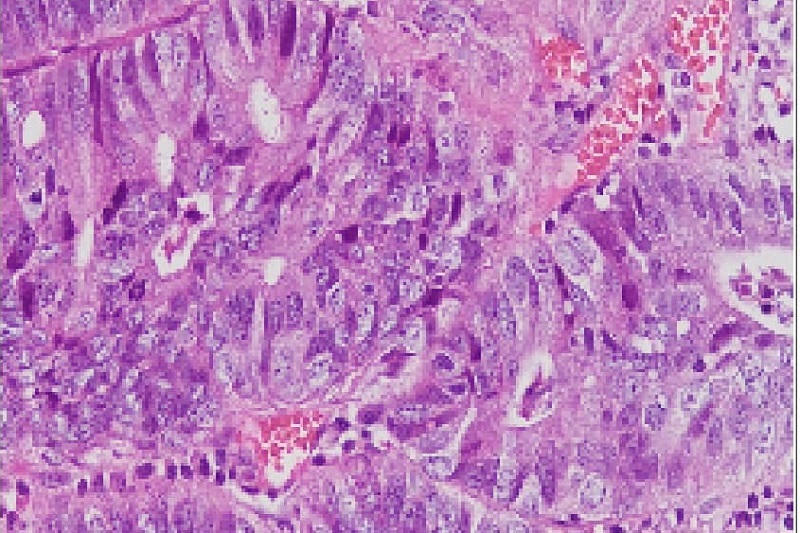

Sau đó, bệnh nhân được nội soi đường tiêu hóa và phát hiện một vài polyp trong đó có các polyp kích thước 1cm. Rất may mắn cho bệnh nhân kết quả sinh thiết polyp là polyp u tuyến ống kèm loạn sản biểu mô độ thấp (khối u lành tính).

Nội soi đại tràng đã phát hiện một polyp có cuống, nhưng bệnh nhân được bác sĩ sử dụng phương tiện can thiệp để cắt polyp ngay trong quá trình nội soi, đồng thời lấy mẫu sinh thiết polyp làm giải phẫu bệnh. Kết quả sinh thiết trả lời là ung thư biểu mô tuyến. Tuy nhiên, đây là một trường hợp đặc biệt, polyp mới bắt đầu chuyển dạng sang ác tính, diện cắt chân polyp không có tế bào ác tính, hay nói cách khác đây là một trường hợp ung thư sớm đã được phát hiện và điều trị triệt để.